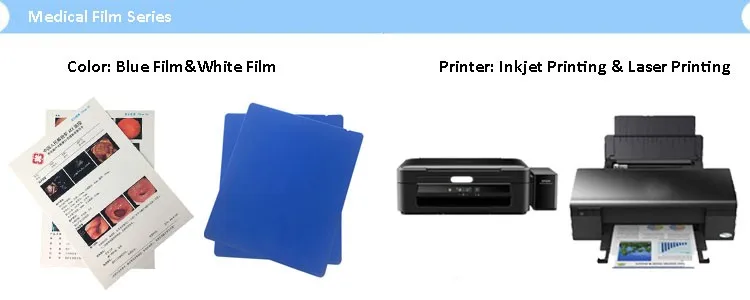

Лазерная камера сетевая для печати изображений на пленке стандарт dicom